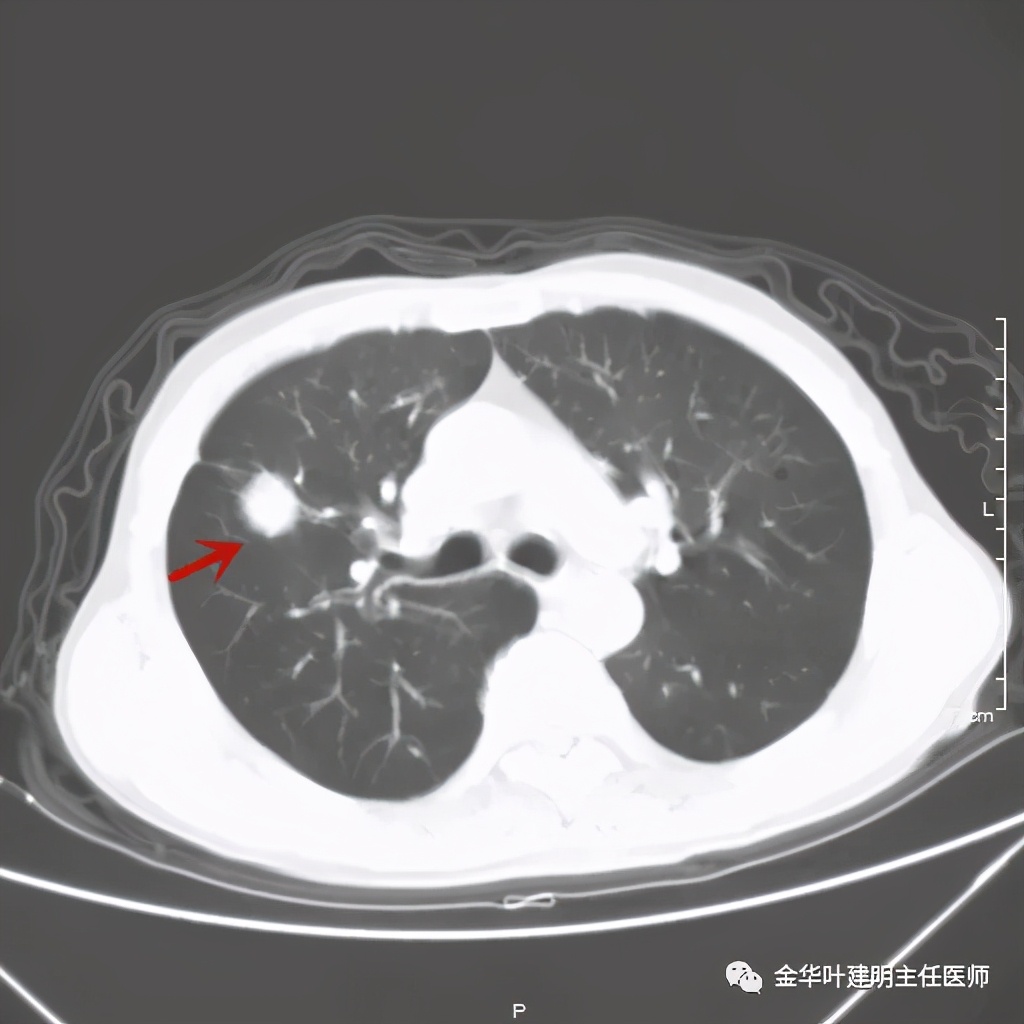

金华的某A,今年73岁,男性。检查发现右上肺占位,肿瘤筛查指标正常,血常规与CRP正常,临床有反复咳嗽、咳痰2年余(考虑慢支的关系,近期也许同时有病灶的影响)。一年前还在外院做过支气管镜,也未见确切异常。我们先来看他这次的胸部CT图像:

上图示病灶

上图桔色箭头示血管进入病灶,较粗;紫色箭头示病灶与胸膜间似乎有所牵拉;红色箭头示病灶